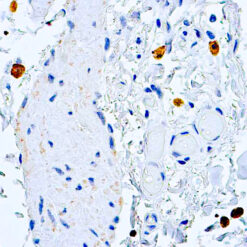

Prostate Specific Antigen, PSA

This product is intended for qualitative immunohistochemistry with normal and neoplastic formalin-fixed, paraffin-embedded tissue sections, to be viewed by light microscopy. Clinical interpretation of staining results should be accompanied by histological studies with proper controls. Patients’ clinical histories and other relevant diagnostic tests should be utilized by a qualified person(s) when evaluating and interpreting results.

| Cellular Localization | Cytoplasmic |

| Positive Control Tissue | Prostate carcinoma |